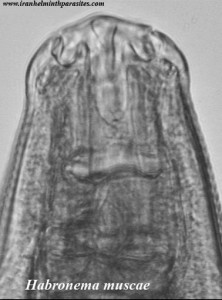

A habronemose é uma helmintose que acomete equídeos (equinos, asininos e muares), e tem como agente etiológico um nematódeo, o Habronema muscae. Ela pode manifestar-se de quatro formas: